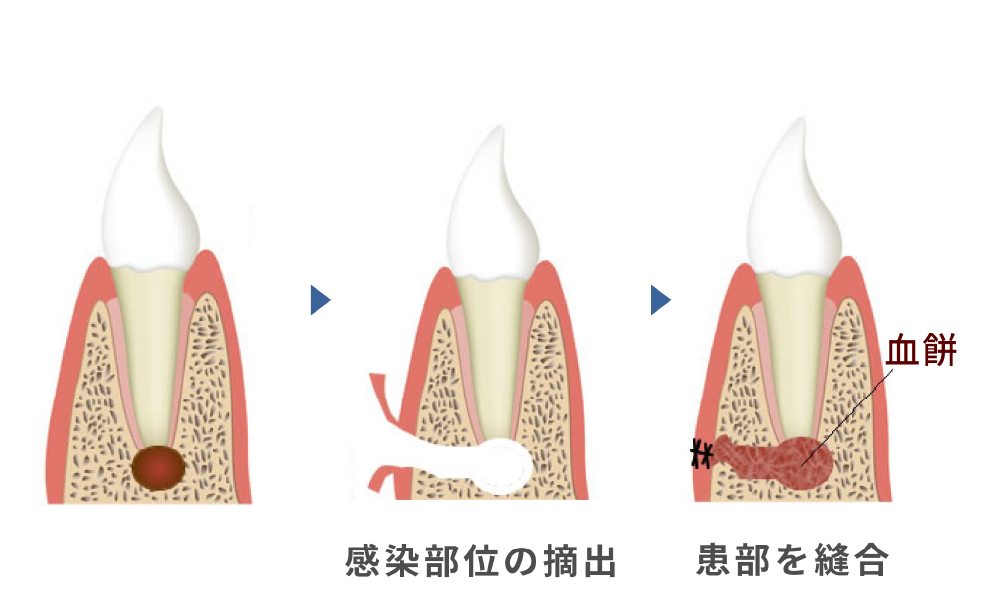

(根尖切除術・意図的再植術)